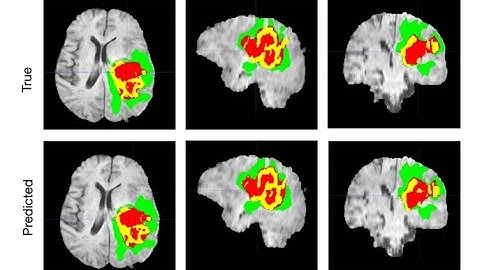

Linknet 3D Brain Tumor Segmentation and Classification Tensorflow | UNET | +91-9872993883 for query